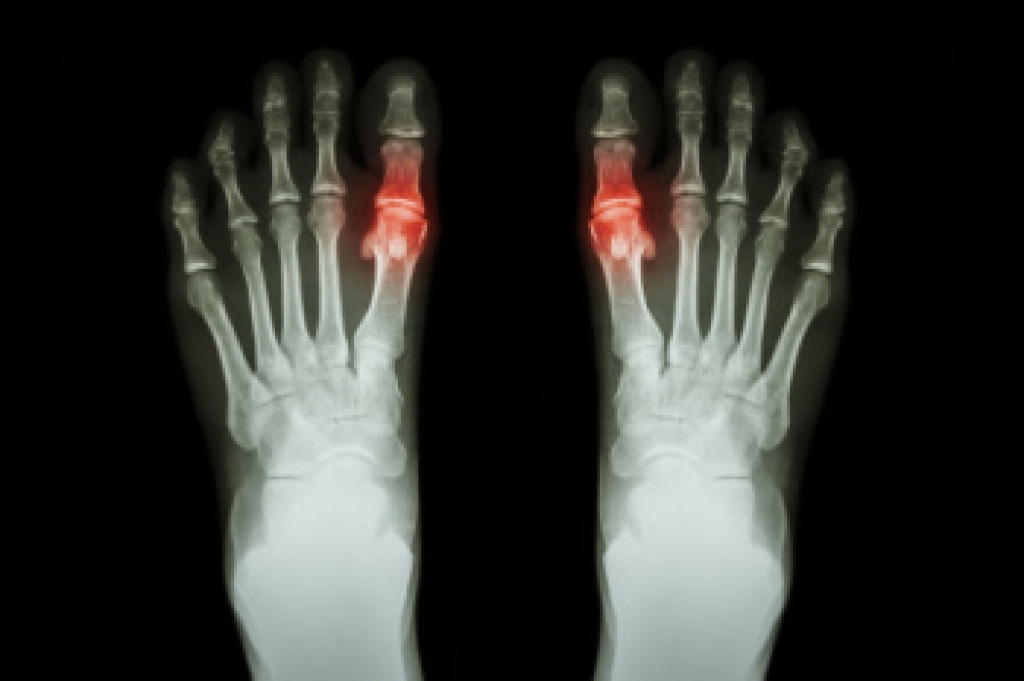

Gout is a form of arthritis caused by uric acid buildup that leads to crystal deposits in the joints. It affects men more often than women, although women become more at risk after menopause. Gout is prevalent worldwide and commonly targets the big toe due to its lower temperature and high pressure put on it during walking. The pain from gout can be severe, and it may be difficult to complete activities. Risk factors include obesity, high purine diets, alcohol use, and certain medical conditions. Symptoms include sudden joint pain, redness, swelling, and tenderness that can limit mobility. A podiatrist can accurately diagnose gout, offer lifestyle guidance and treatments to manage pain and prevent recurrence. If you have symptoms of gout, it is suggested that you consult a podiatrist who can help you to manage this painful condition.

Gout is a type of arthritis caused by a buildup of uric acid in the bloodstream. It often develops in the foot, especially the big toe area, although it can manifest in other parts of the body as well. Gout can make walking and standing very painful and is especially common in diabetics and the obese.

Gout can easily be identified by redness and inflammation of the big toe and the surrounding areas of the foot. Other symptoms include extreme fatigue, joint pain, and running high fevers. Sometimes corticosteroid drugs can be prescribed to treat gout, but the best way to combat this disease is to get more exercise and eat a better diet.